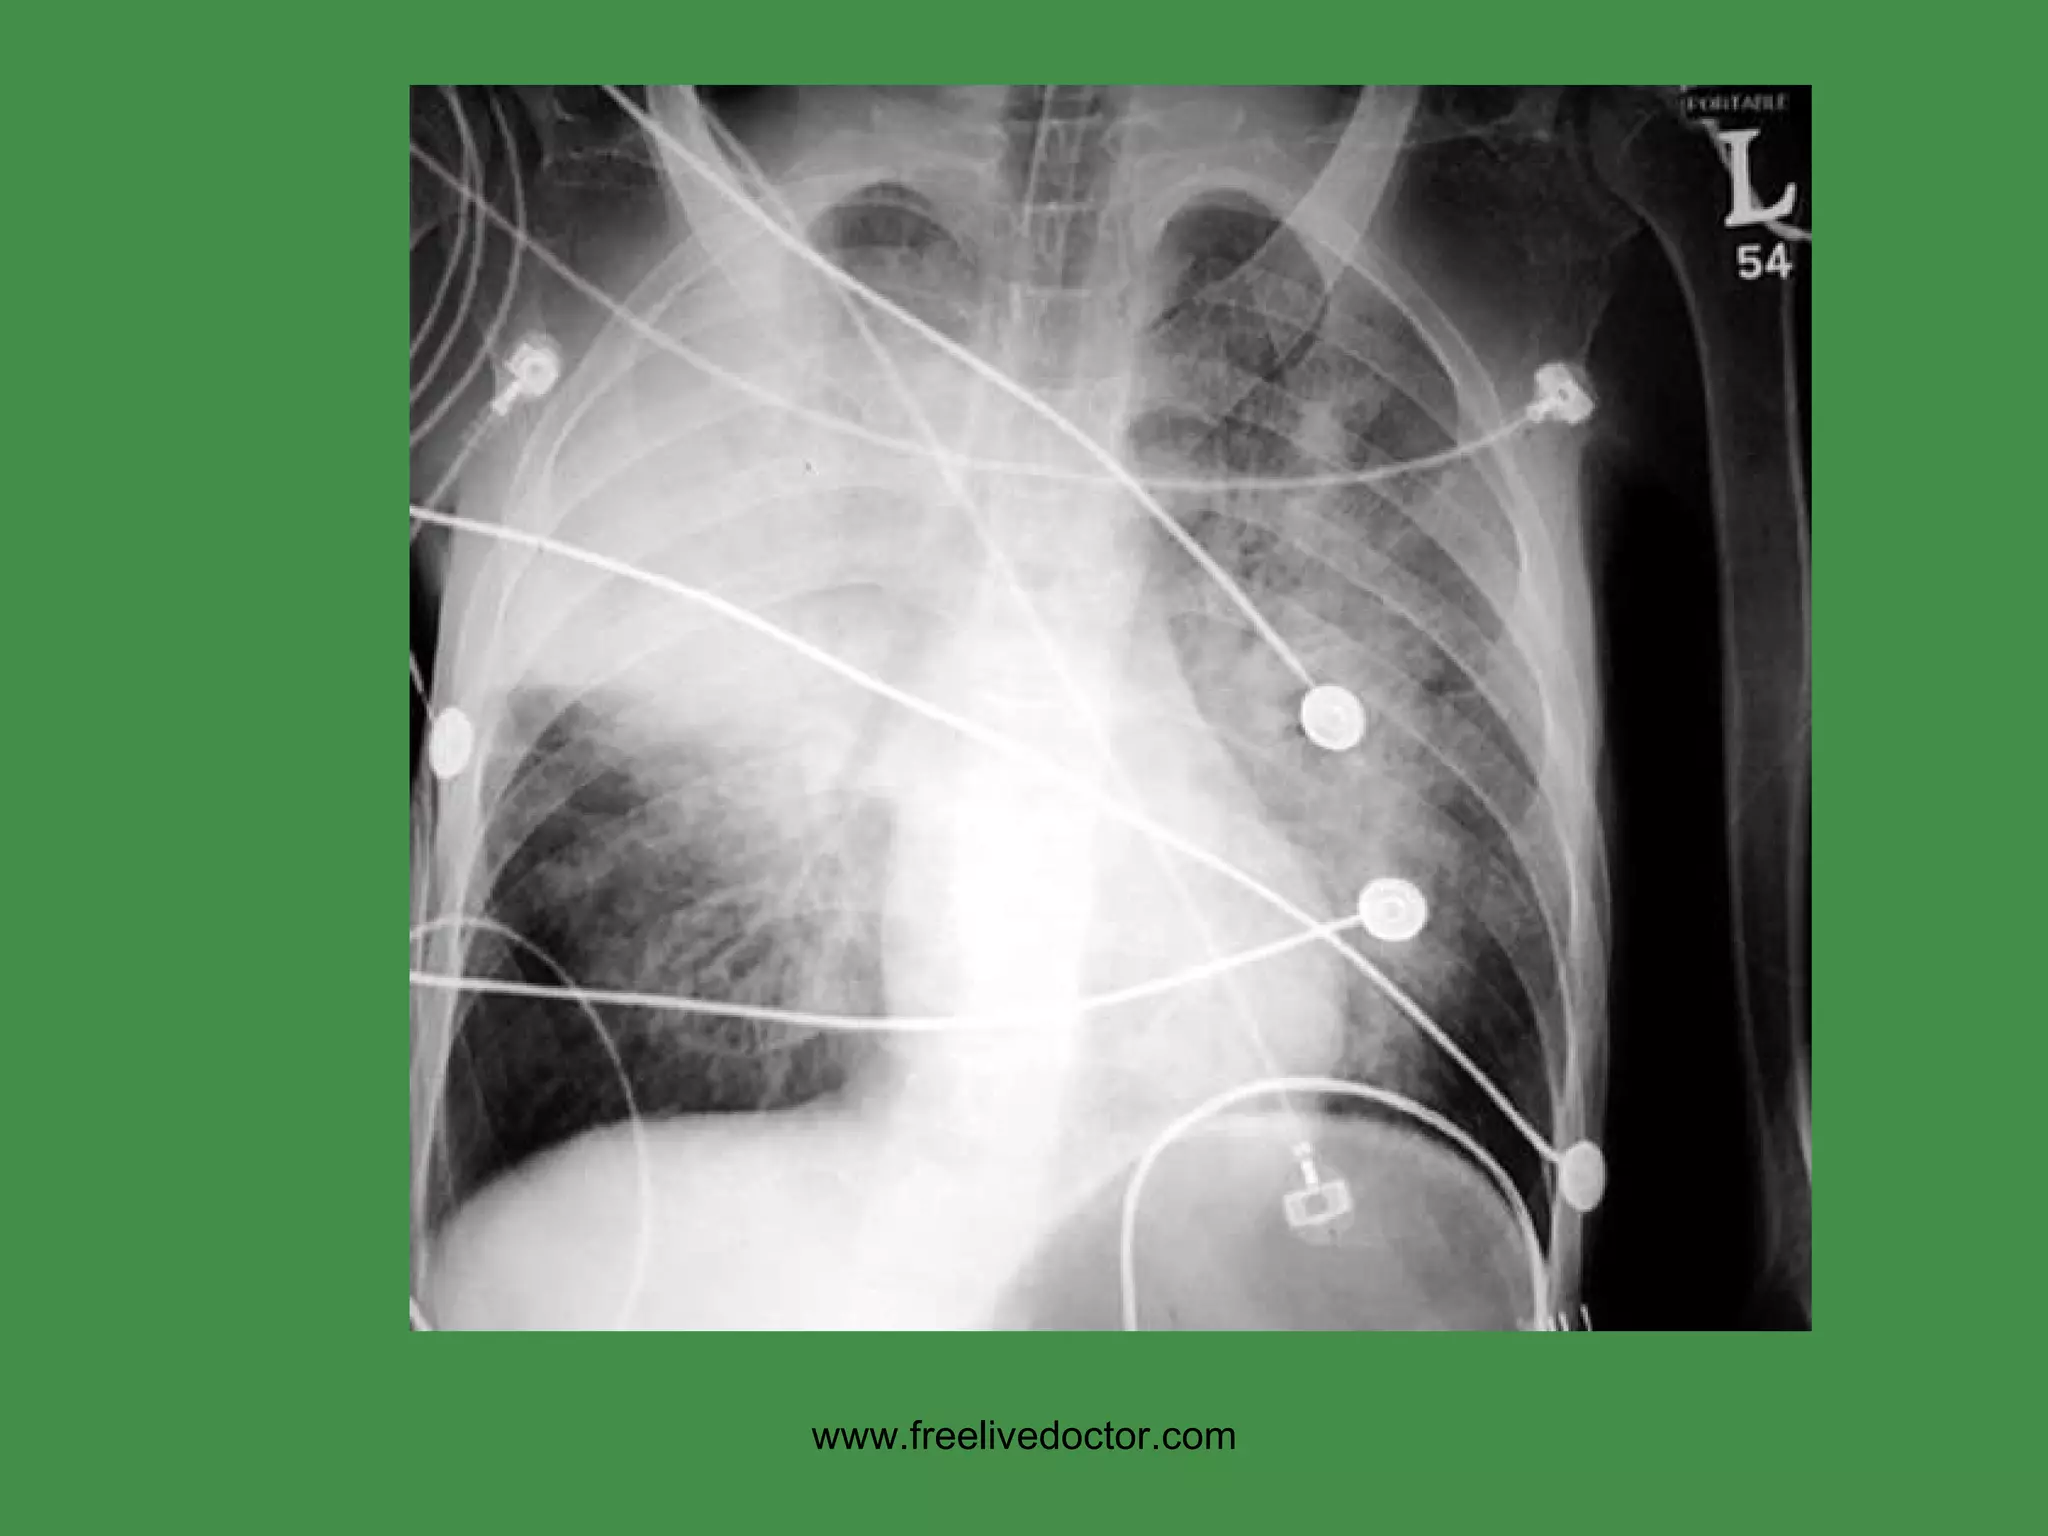

www.freelivedoctor.com NORMAL” chest X-Ray [CXR]

• #10 “ NORMAL” chest X-Ray (CXR)